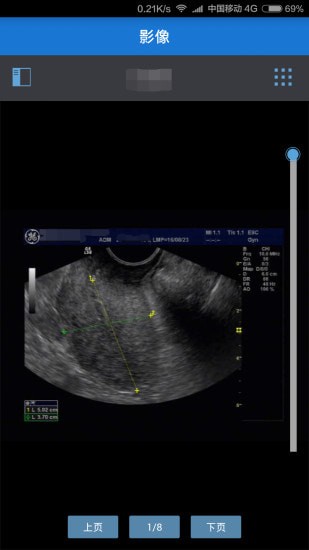

3、影像

支持检车影像在线预览